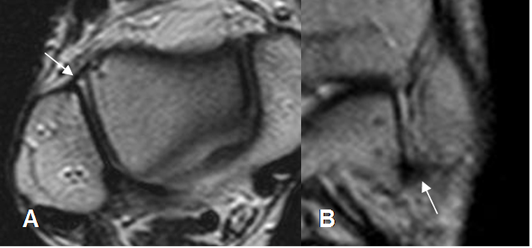

Fig 12. Ligamento peroneocalcáneo normal.

A: RM axial y B: RM coronal en T2.

Fig 13. Ligamento tibioastragalino anterior normal.

A: RM axial en T2 y B: RM coronal en T1.